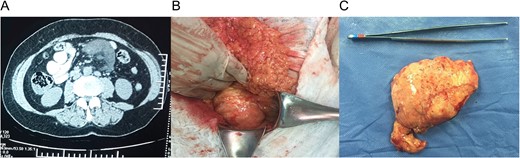

She had normal blood work, and a contrast-enhanced abdominal computed tomography (CT) revealed a 9 × 7 × 4 cm3 mass within the small bowel mesentery near the root of the mesentery with several lymph nodes surrounding it. No other lesion or masses were found (Fig. 1A).

(A) Computed tomography (CT) with a 9 × 7 × 4 cm mass within the small bowel mesentery near the root of the mesentery. (B) Mass in the root of small bowel mesentery near the mesenteric vessels. (C) External surface of the mass.

With these findings, surgery was decided and at laparotomy, a 9, 5 × 7 × 5 cm3 mass was discovered in the root of small bowel mesentery, near but not in contact with major vessels, it was completely resected with a 0.5 cm margin, respecting bowel wall and vessels (Fig. 1B).

The external surface of the mass had a yellowish like-fat aspect and contained white milky fluid, the mass contained some cystic lesions and the wall was 0.5 cm in width (Fig. 1C). Pathology reported encapsulated fat tissue surrounded by dilated lymph vessels that contained lymphocytes. Immunohistochemical study for D2-40 was positive. Lymphangioma cavernous was the final diagnostic (Fig. 2A–C).